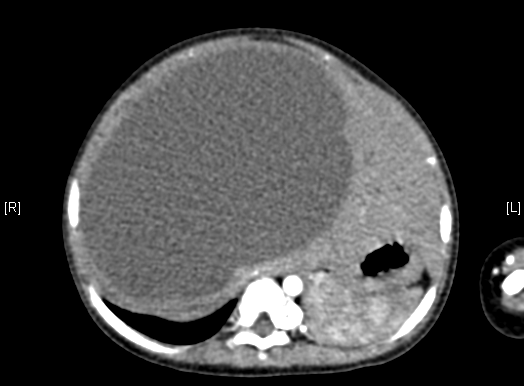

上腹部增强CT:肝右叶囊实性占位。上腹部增强CT示间叶性错构瘤。

术前CT检查:

动脉期

静脉期

平衡期